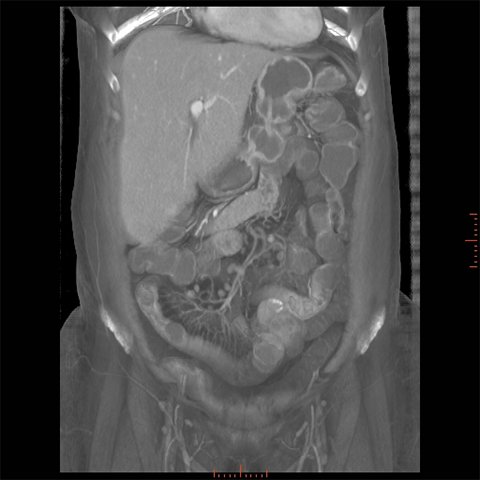

56 year-old male with Crohns Disease presents with persistent abdominal pain and diarrhea. [4 of 4]